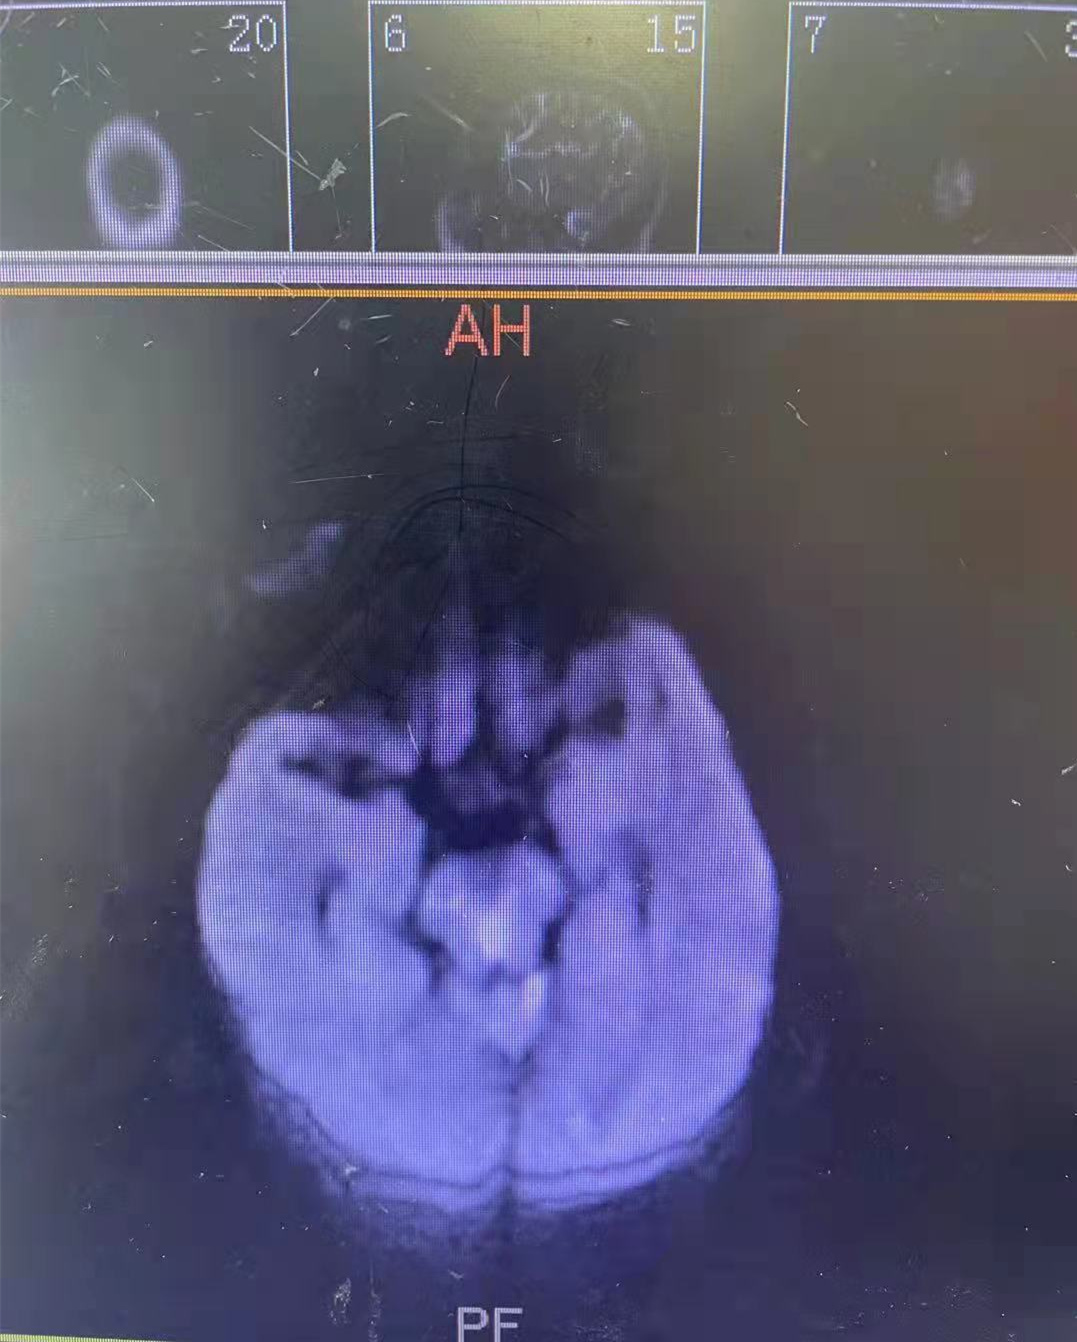

★双侧椎动脉严重狭窄

★ 脑干、小脑、丘脑梗死(多发)

患者鞠大爷,78岁,因“突发意识不清2小时”,于9月6日 急诊入住神经内二科。值班医师迅速接诊,查体:呼吸急促,深昏迷状态,双侧瞳孔不等大,右侧瞳孔直径约5mm,左侧瞳孔直径约2mm,调节及对光反射均消失,四肢肌力刺激无反应,四肢肌张力高。右侧巴氏征阳性,ESSEN评分3分,NIHSS评分25分。主任医师赵海滨凭借多年临床经验,考虑患者为基底动脉闭塞导致的脑干梗死。该疾病死亡率极高,彼时患者生命体征不稳,情况紧急,待评估患者病情后,赵主任立即向家属说明病情,并及时给予阿替普酶静脉溶栓术。在医护人员的缜密配合下,溶栓后1小时,患者神志转清,呼吸平稳,言语清晰,四肢肌力恢复IV级。经过14天精心治疗,鞠大爷活动自如,精神状态良好,康复出院之际,患者及家属特意到医生办公室感谢赵海滨主任及各位医务人员的及时救治。